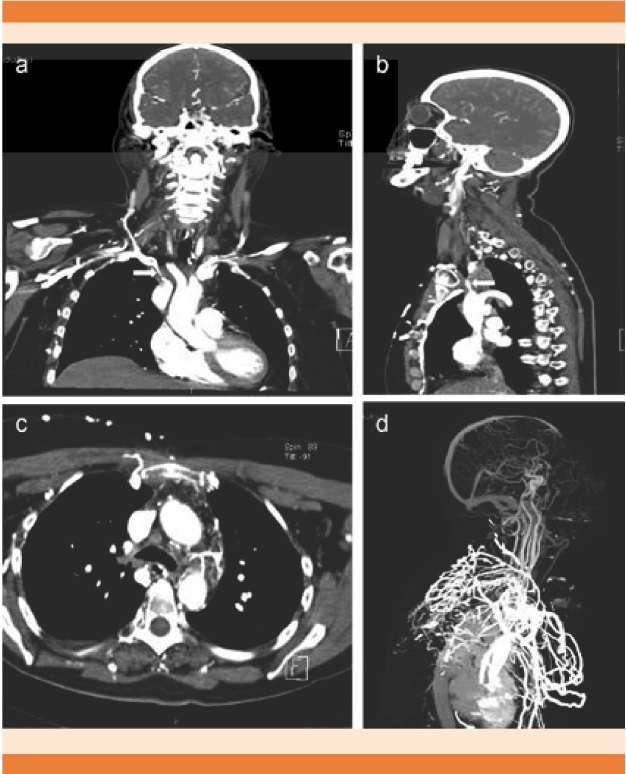

Para fines prácticos, las causas que condicionan obstrucción de la vena cava superior y por consiguiente el síndrome de la vena cava superior, se clasifican en benignas y malignas (Cuadro 1). Las causas se han modificado con el paso del tiempo y las causas benignas tienden al incremento. Hace algunas décadas, las infecciones por sífilis, tuberculosis e histoplasmosis eran la mayor causa de los casos del síndrome de la vena cava superior. A inicios de la administración de los antimicrobianos estas enfermedades dejaron de formar parte de las principales causas benignas.10 La trombosis concomitante con lesión vascular iatrógena durante la colocación de accesos vasculares se asocia, incluso, en 71% de las obstrucciones benignas de la vena cava superior (Figura 5); en segundo lugar, se encuentra la fibrosis de mediastino secundaria a infecciones y radioterapia.11

Figura 5 Paciente de 49 años con síndrome de la vena cava superior benigno por aneurisma de vena subclavia derecha secundario a colocación de catéter (Mahurkar®) de hemodiálisis. A. Radiografía de tórax con ensanchamiento de mediastino (chevrones) y borramiento de la línea paratraqueal derecha (asterisco). B y D. Aneurisma contenido que comprime la vía aérea y las estructuras vasculares adyacentes. C. Compresión casi total de la vena cava superior (flecha).